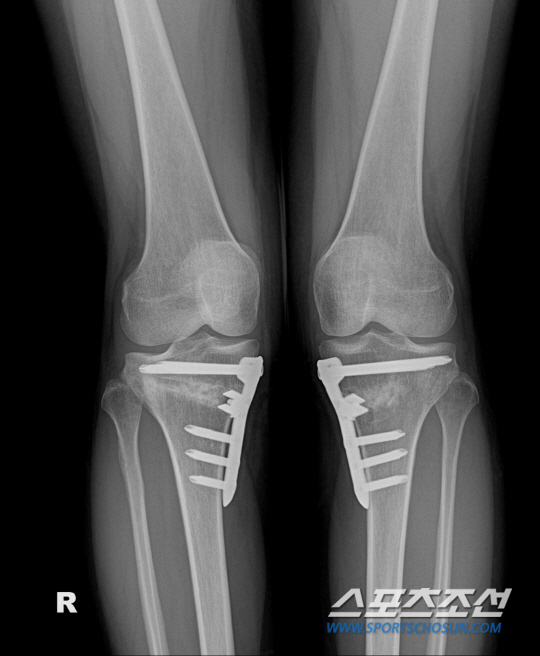

휜다리수술로 알려진 근위경골절골술은 휘어진 다리를 바르게 교정하여 무릎 내측에 집중되어 있는 무게 중심을 고르게 분산시키는 교정 수술이다. 환자가 비교적 젊은 경우(대체적으로 70세 이하), 무릎 안쪽에 퇴행성관절염인 경우, 초·중기 관절염인 경우에 적용되며 이 시기 수술의 예후가 좋다.

권제호 바른세상병원 원장은 "근위경골절골술은 휘어진 무릎을 동반한 40~60대 환자들 중 인공관절을 적용해야 할 만큼의 말기 퇴행성관절염 환자에게도 적용이 가능하다"며 "인공관절수술과는 다르게 자기 관절을 보존하는 수술이므로 수술 후에도 정상 관절과 같이 무릎의 관절각도에 제한이 없고 재활 후에는 등산과 같은 운동도 가능하다"고 말했다.